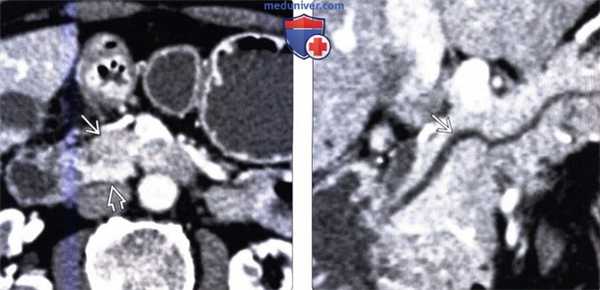

(Слева) На аксиальной КТ в артериальной фазе контрастного усиления в передних отделах головки поджелудочной железы визуализируется гиподенсный участок, хорошо отграниченный от окружающих тканей. Обратите внимание, что крючковидный отросток, расположенный сзади, накапливает контраст так, как это и должно быть в норме.

(Справа) На КТ (реформатирование в плоскости панкреатического протока) патологических изменений со стороны протока не определяется. Типичное расположение и отсутствие объемного воздействия на проток являются ключевыми признаками, позволяющими сделать заключение о очаговой жировой инфильтрации.

(Справа) На КТ (реформатирование в плоскости панкреатического протока) патологических изменений со стороны протока не определяется. Типичное расположение и отсутствие объемного воздействия на проток являются ключевыми признаками, позволяющими сделать заключение о очаговой жировой инфильтрации. (Слева) На аксиальной МР томограмме (градиентное эхо в «фазе») интенсивность сигнала в головке поджелудочной железы выражена равномерно.